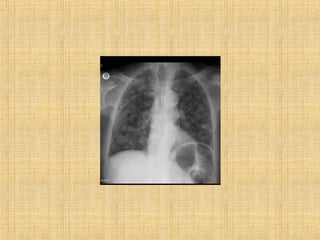

As principais informações do documento são: 1. Discute os padrões de doença pulmonar causados por metástases, incluindo nódulos, espessamento intersticial e obstrução das vias aéreas. 2. A prevalência de metástases pulmonares varia de 30-55% dependendo do tumor primário, e são mais comuns em pacientes acima de 50 anos. 3. Os achados clínicos mais comuns são dispneia, hemoptise e febre, enquanto exames de escarro ou lavado brô